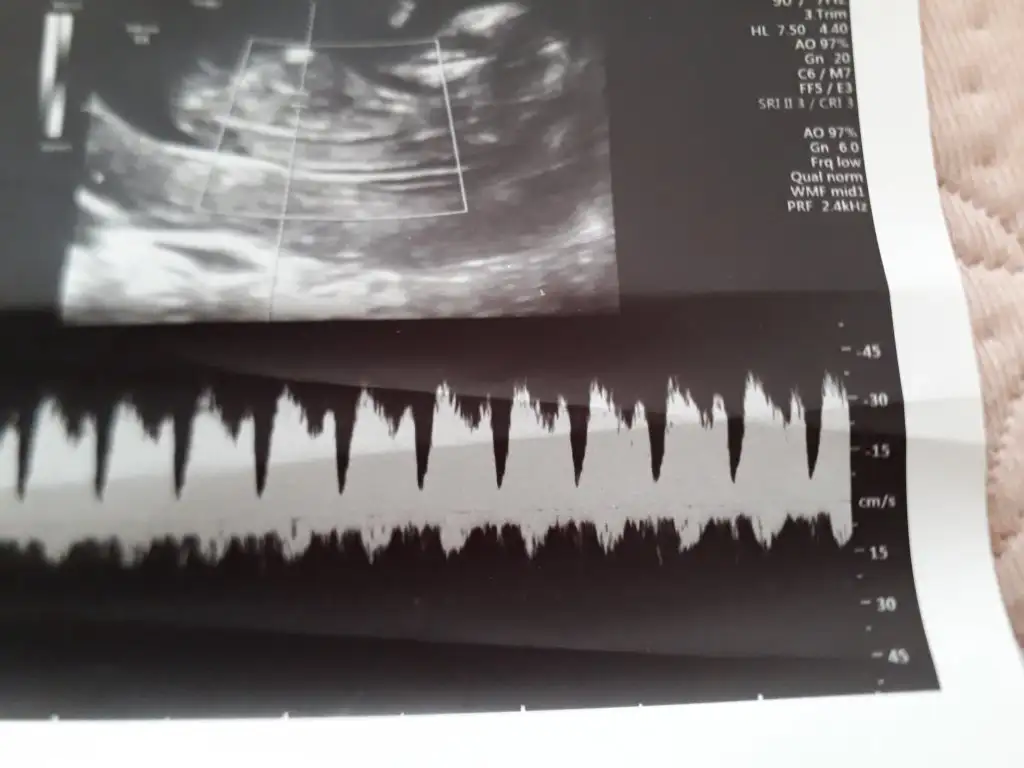

ikili tarama sonrası. Sizce cinsiyeti nedirr? Doktor bi tahmin de bulundu ama daha erken tabi ☺️☺️

ikili tarama sonrası. Sizce cinsiyeti nedirr? Doktor bi tahmin de bulundu ama daha erken tabi ☺☺

Usg net değil emin olmadım başka usg de paylaşın 12 13 hafta olursa şimdilik sanki erkek gibi gibi 😬

Kız sanki burada nubu ne dik nede paralel karşıya bakıyor 😊 önceki usgde erkek gibiydi 😄

😂 Tahminim kız ama daha tam oluşmamış üç haftası var oluşması icin dedi doktor.tabi ki hayırlısı olsun saglıklı hayırlı evlat olsun ama gönlümden gecen kız olması bakalım bekleyip görücez.tesekkürler tahmininiz için ❤️